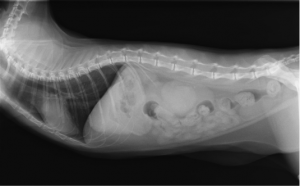

術前のレントゲン

VD像では不明瞭だがラテラル像にて腎臓の尾側に結石が確認できます。